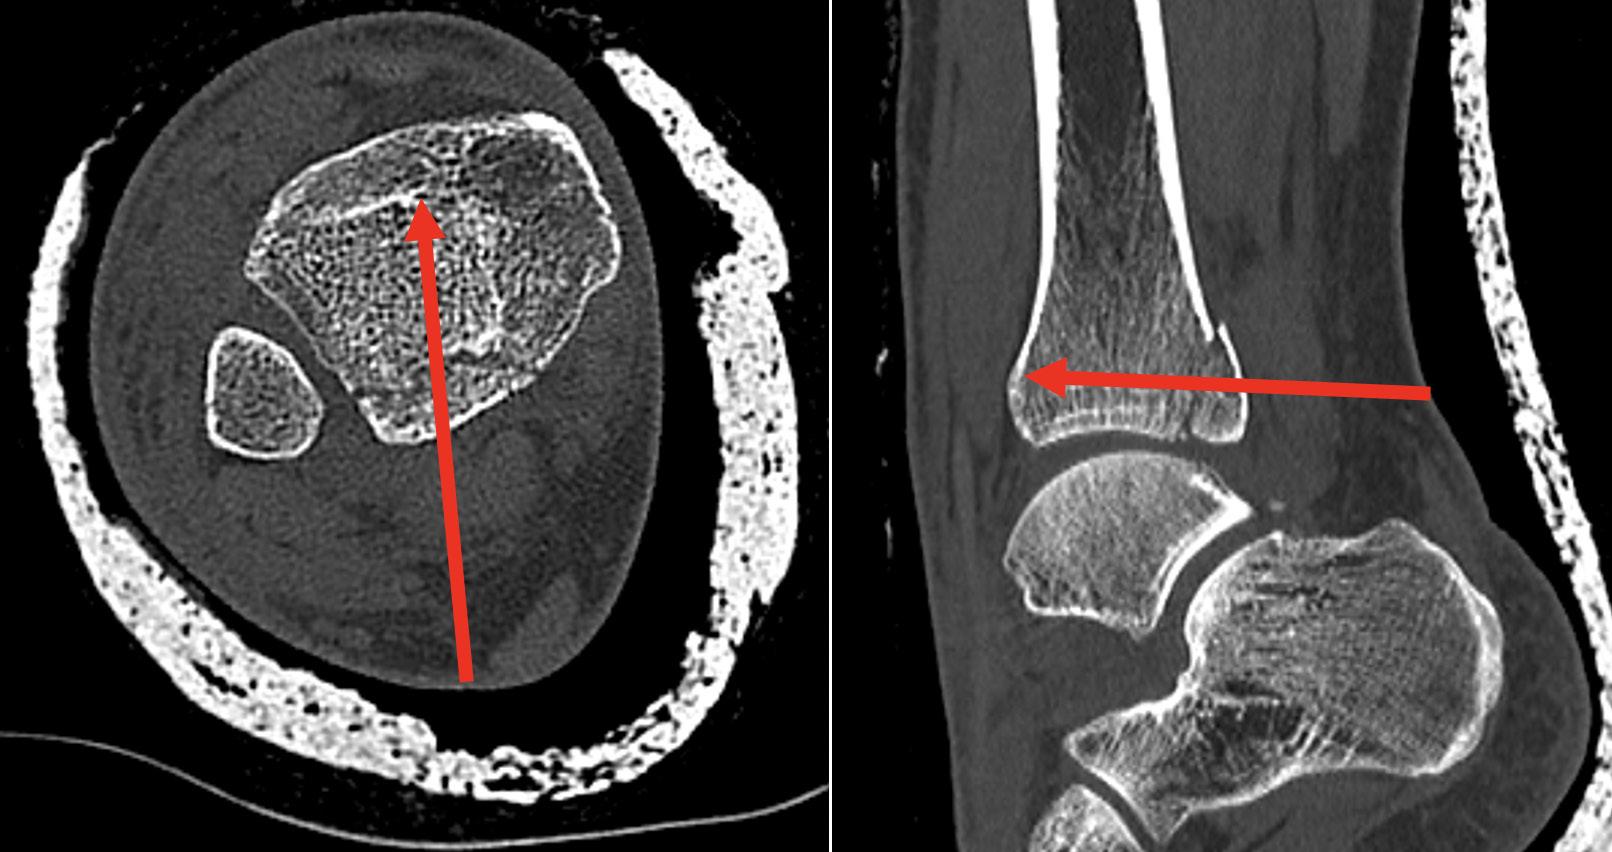

Posterior malleolar fractures (PMFs) account for up to 50% of ankle fractures when assessed with CT. The historical “one-third rule” guided fixation by fragment size; however, morphology and stability are now recognised as more important determinants of outcome.

The MPM approach allows good visualisation of the posterolateral,

posteromedial and medial (with anterior extension) aspect of the tibia. In comparison the PL approach allows access to a small aspect of the posterolateral tibia and the fibular (figure 2). Direct comparison of the exposures has shown almost double the surface area exposed by the MPM as compared to the PL1.

2. Soft-tissue Entrapment Clearance

PTT entrapment has been found in over 40% of PMFs when the fracture line enters the PTT sheath2. In the MPM approach, the PTT sheath is visualised, entrapment can be identified and released. With the PL approach, this is not possible.

3. Access to Die-Punch Fragments

Die-punch injuries are common in PMFs and most frequently occur under the posterolateral fragment. The MPM approach allows direct access to the die punch fragment, when the PL does not. It is easier to go through the open door than the hinge.

4. Vascular Safety

Vascular studies have shown two important aspects regarding the risks posed by the PL approach3. Firstly, the flexor hallucis longus (FHL) muscle is supplied by up to six perforators from the peroneal artery. By moving the FHL medially to get access to the posterior tibia during the PL approach, the FHL is moved away from the peroneal artery and can therefore lose its blood supply and become necrotic. If you have seen a FHL contracture following a PMF fixation, this is the reason.

Lyndon Mason Consultant, NHS University Hospitals of Liverpool Group; Honorary Associate Professor, University of Liverpool

The risk increases, the longer the incision. Secondly, and more importantly, in a twovessel limb (dominant peroneal artery and anterior tibial), the blood supply to the foot is supplied by a communicating vessel connecting the peroneal and tibial arteries (figure 3). This communicating branch is very commonly sacrificed in the PL approach If this is sacrificed in a two vessel limb, this can result in an avascular foot4. The MPM comes anterior to the FHL and communicating branch and does not have these risks.

Recent CT-based studies have reported >90 % anatomical reduction within >>

2mm and >90 % syndesmotic congruity after MPM fixation, however other studies using PL approach only achieve approximately 50% anatomical reduction5, 6 Our own data has shown complication rates up to 66% following PL fixation, compared with 8% using MPM when using the Clavien-Dido classification for complications.

The MPM approach overcomes the three principal limitations of PL approach, restricted exposure, unaddressed entrapment, and vascular risk. Its direct vision of the posterior and medial tibia enables true anatomical reduction, particularly in die-punch and 2B PMFs. The ability to clear PTT entrapment prevents secondary displacement and pain. Preservation of the posterior vasculature markedly decreases complication rates. Adoption requires anatomical familiarity, but reproducibility and outcomes justify its broader implementation. In my view, due the vascular risks of the PL approach specific to a two-vessel limb, continued use of the PL approach should instigate a CT angiogram pre-surgery.

Figure 3: CT angiogram pre fixation of a PMF, showing a 2-vessel leg due to sclerosis of the posterior tibial artery, where the peroneal artery becomes dominant through the communicating branch.